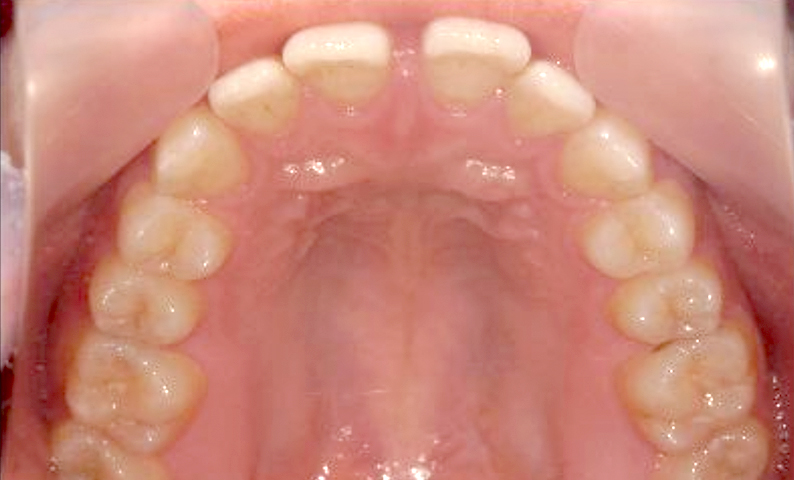

| 治療前 | 治療後 |

|---|---|

|